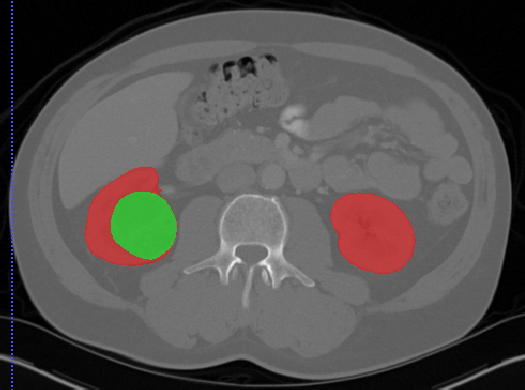

肾脏

Kits19

| Kits19 | 肾肿瘤 | 分割 |